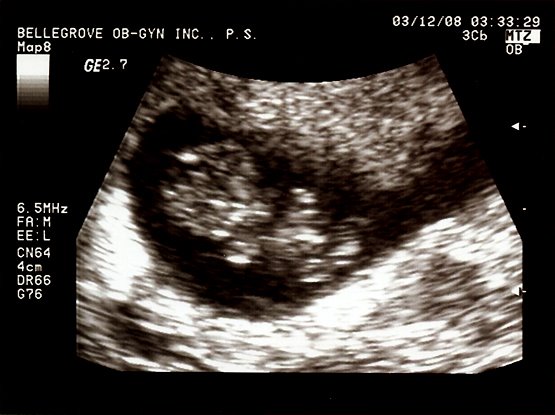

Alright, its off to bed for some much needed sleep. Even the baby is tired! Take care and we will update when there is more to tell! Lots of love from all of us!